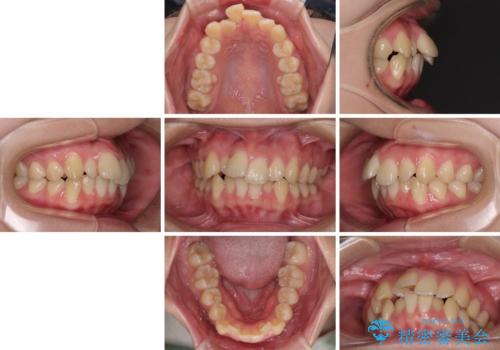

- 前歯のデコボコと突出感を気にして来院された患者様です。

上下左右第一小臼歯4本を抜歯して、積極的に口元を引っ込めるよう、ワイヤー装置にて矯正治療を行うこととしました。